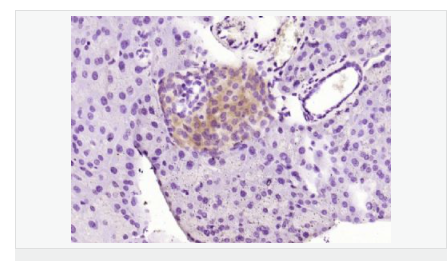

| 产品应用 | WB=1:500-2000 ELISA=1:5000-10000 IHC-P=1:100-500 IHC-F=1:100-500 IF=1:100-500 (石蜡切片需做抗原修复) not yet tested in other applications. optimal dilutions/concentrations should be determined by the end user. |